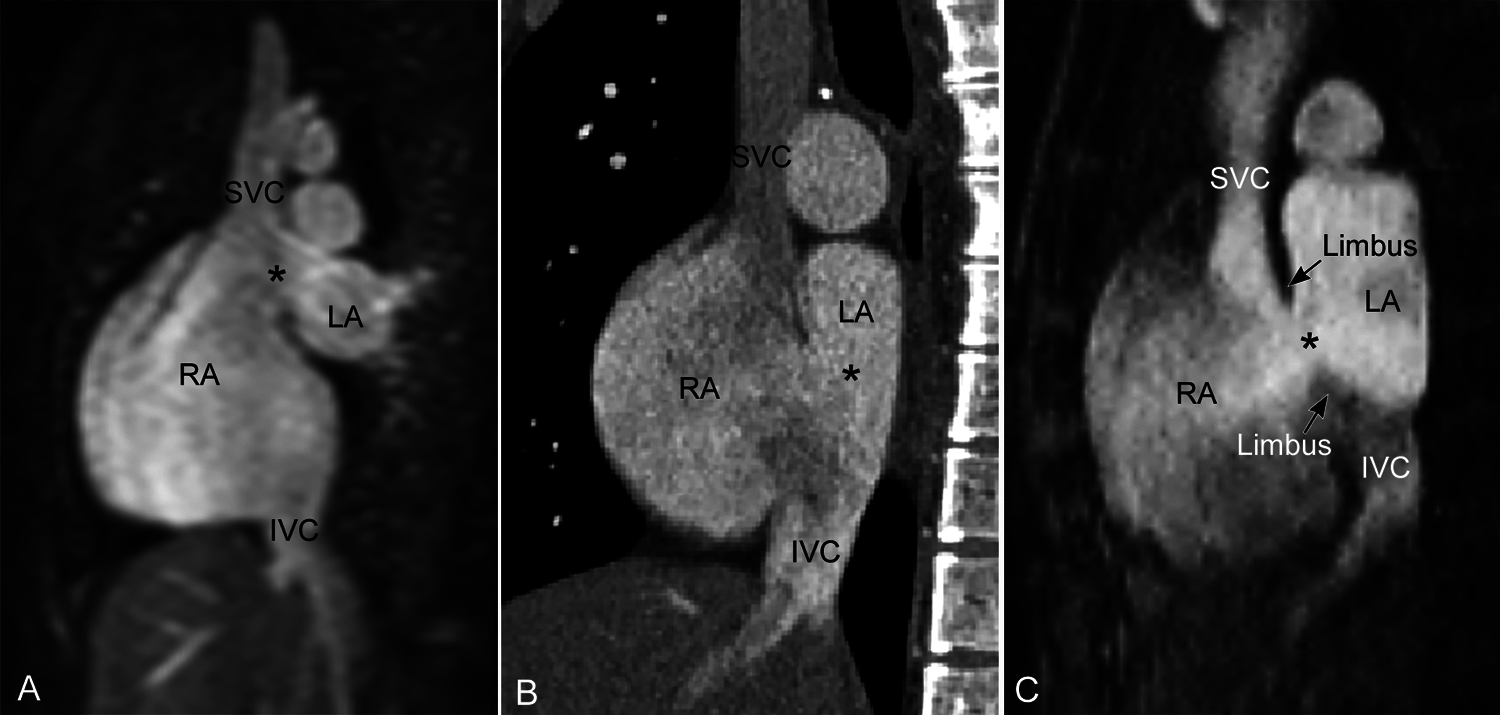

Figure 8: Superior (A) and inferior (B) sinus venosus defects and secundum atrial septal defect (C) shown in parasagittal intercaval or bicaval view. The superior and inferior sinus venosus defects (asterisk) involve the uppermost and lowermost parts of the septum seen in this view. The superior sinus venosus defect in A is not associated with overriding of the superior vena cava across the atrial septum. The inferior sinus venosus defect in B is associated with overt overriding of the inferior vena cava across the atrial septum. This finding is due to the alignment of the affected part of the septum along the trajectory of the inferior vena cava rather than any malalignment of the atrial septum or inferior vena caval orifice. A defect involving the floor of the fossa ovalis (secundum atrial septal defect) may be seen in this view but is bordered by the limbus on both margins as shown in C. IVC, inferior vena cava; LA, left atrium; RA, right atrium; SVC, superior vena cava

The inferior sinus venosus defect affects the lowermost convex part of the interatrial party wall along the sinus venarum. Invariably, the inferior vena cava appears to connect to the left atrium or override the defective atrial septum above. One may speculate malalignment of the atrial septum or malposition of the inferior vena cava as the underlying mechanism for overriding of the inferior vena cava. However, the position of the inferior vena cava and the orientation of the intact part of the atrial septum are not different from those of normal hearts. Overriding of the inferior vena caval orifice is due to the presence of a hole in the interatrial party wall that is normally in the trajectory of the course of the inferior vena cava (Fig. 6). A hole in the sloping posterior inferior part of the interatrial party wall simply lets the vena cava appear to connect to the left atrium especially when the Eustachian valve is prominent (Figs. 11 and 12).